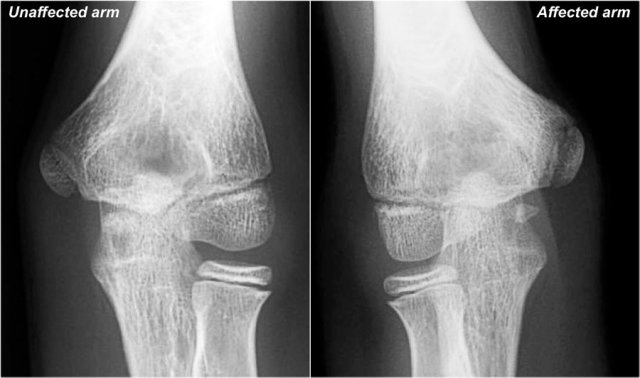

Little Leaguer's Elbow

First study the images of a patient with pain on the medial side, then continue reading...

The findings are very subtle.

The medial epicondyle of the affected arm is somewhat more osteopenic.

In these cases we usually ask for a comparison view, because it can be very subtle.

The diagnosis is a Little leaguer's elbow which results from chronic stress injury.

The lucency on the radiograph, which looks like a widened physis, is due to cartilage ingrowth in the metaphysis.

Continue with the MR...

On the MR the abnormality is very obvious.

There is marrow edema in the medial epicondyle and also in the adjacent bone (yellow arrow).

Little Leaguer's elbow is also known as medial apophysitis and some call it epiphysiolysis.

By the way this could also be called a Salter-Harris type I fracture, if it was an acute traumatic event.

Notice the normal ulnar collateral ligament (red arrow).

In children the weak link in valgus stress is not the ulnar collateral ligament but the physis.